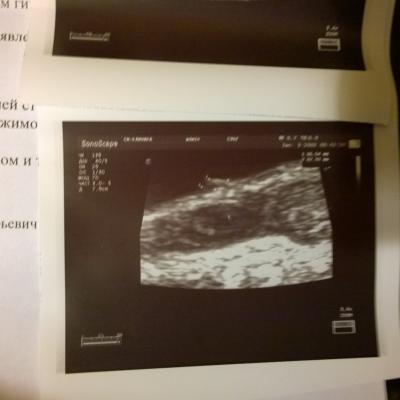

Образование в мочевом пузыре

Здравствуйте. При узи МП нашли образование на нижней стенке, фото прилагаю.

Насколько вероятно, что это доброкачественное? Анализ крови-повышен гемоглобин 161, моноциты 12%. в Моче эритроциты 9-10 в п\з, лейкоциты 2-3 в п\з